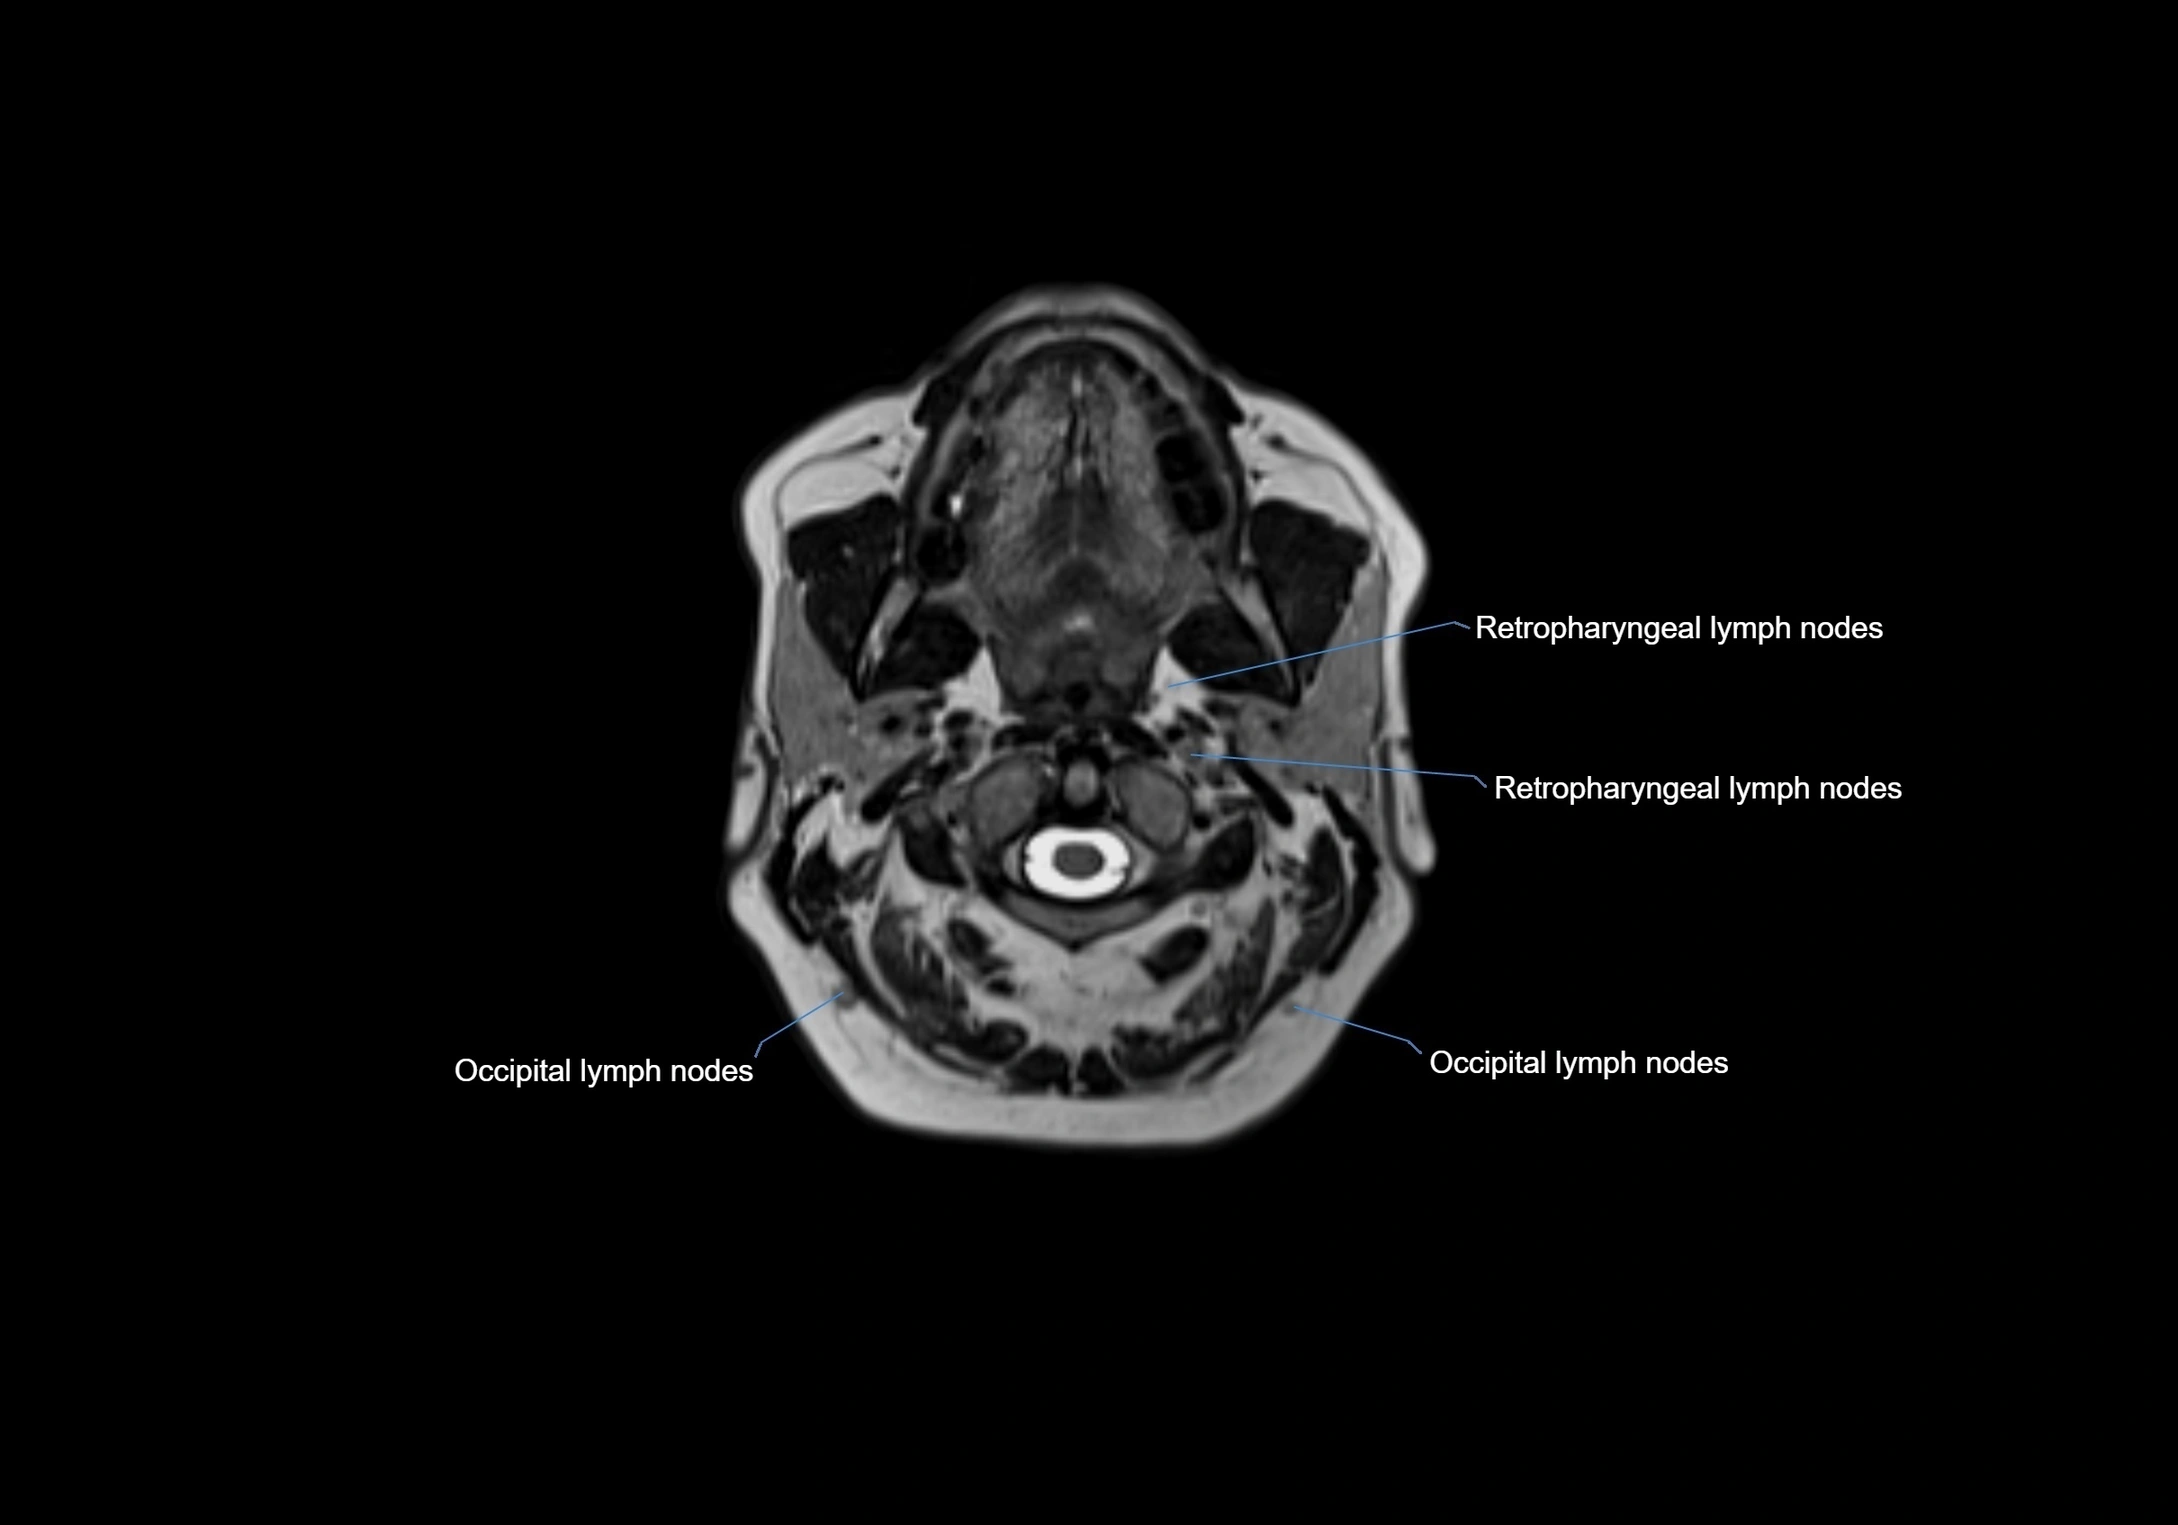

Location

• Found along primary lymph node chains, including preauricular, submandibular, parotid, and occipital regions

• Embedded in subcutaneous fat or superficial fascia, often lateral or posterior to primary nodes

• Variable in number; may occur unilaterally or bilaterally, depending on individual anatomy

CT Appearance:

• Nodes appear as small, soft tissue density structures embedded in subcutaneous fat near primary lymph nodes

• Surrounded by air in adjacent facial cavities or normal soft tissue, providing natural contrast

• Enlarged or pathological nodes appear as well-defined or irregular soft tissue masses

• CT is particularly useful for preoperative assessment, infection evaluation, or detection of metastatic spread